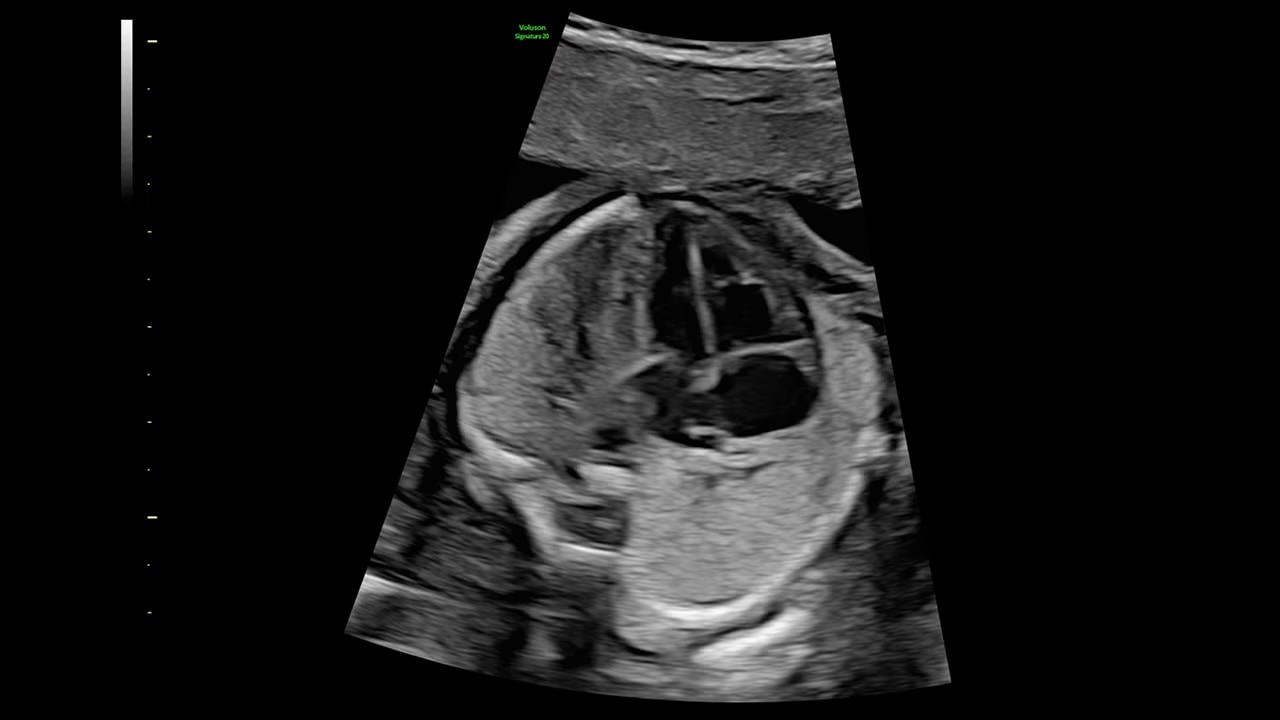

Decreases shadows on B-mode imaging which can obscure adjacent structures by helping to restore tissue information and borders.